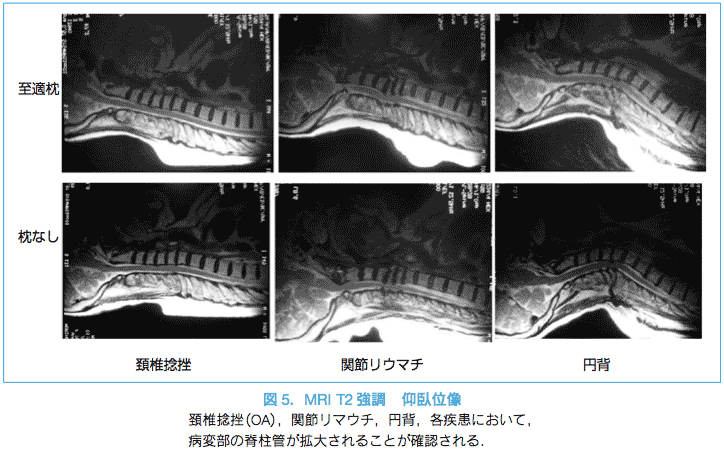

まず始めに頚椎および頚髄の矢状面アライメントを解析した。仰臥位頚椎傾斜角とは、仰臥位頚椎の矢状面アライメントの指標の1つとして当院で考案した角度である。大後頭孔前縁中点と第7頚椎の椎体後面を結ぶ線と、臥床面のなす角である。正常例のみならず関節リウマチの環軸椎亜脱臼例においても延髄~頚髄のアライメントとして評価できる(図5)。